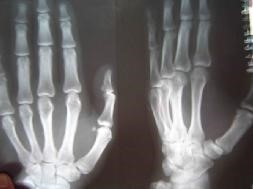

二零零三年三月,邢家秋不堪残酷的摧残,以绝食抗议。在监区队长王晓波、董仑山的指使下,犯人王权、李素安等人在操作间里对他进行围殴。李素安找来一根铁锹把儿,犯人们把他摁倒在地,扒下他的棉裤,分别踩着、摁着他的头、腿、胳膊,李素安抡起锹把猛烈抽打他的腰、臀等部位。因为剧痛,邢家秋用手去挡,手却被李素安抡了一棒,他晕了过去,这时,他的手背肿得像个馒头,不能动。第二天,李素安、金永军对他又一顿毒打,李素安冲着他受伤的手砍了一掌,他痛得坐在地上,此后他的手剧烈疼痛不敢动。

二零零五年六月在沈阳第一监狱拍的X光片子显示邢家秋左手中指骨折